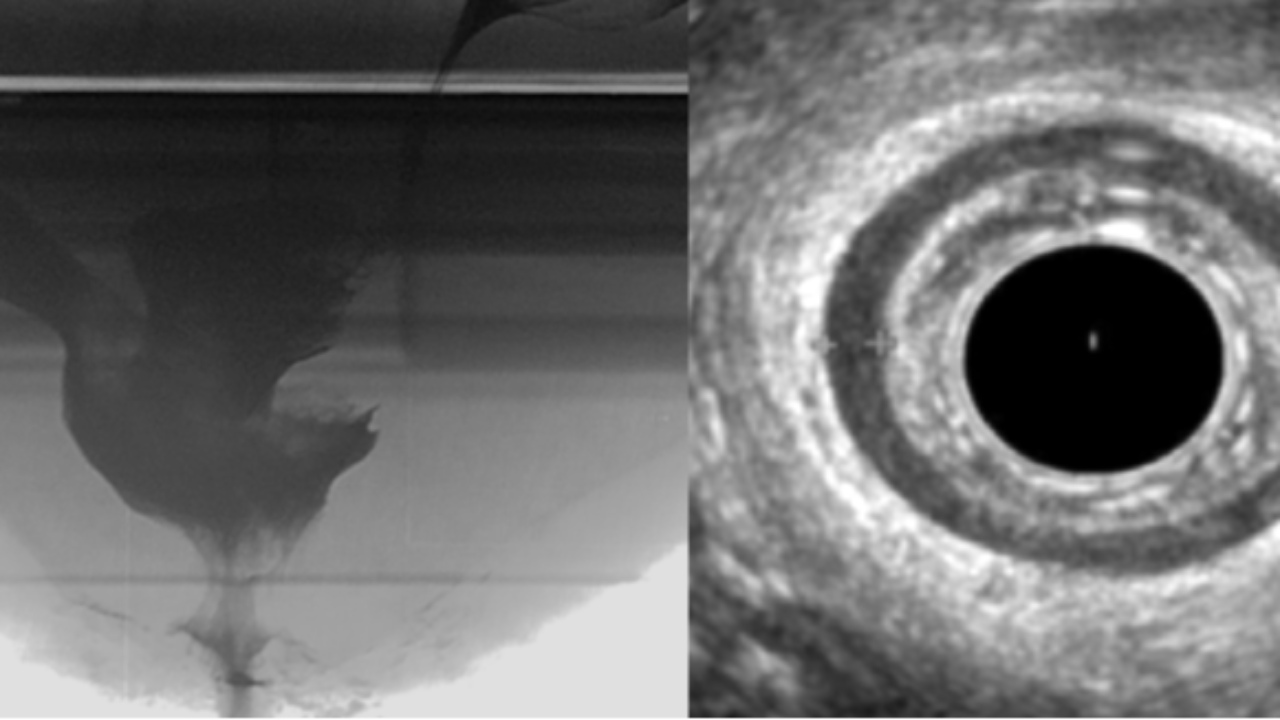

This 10-session live online mentorship programme will take you through a tried and tested fellowship where we will discuss indications, technique, interpretation and limitations of pelvic floor diagnostics, including; 1. Endoanal Ultrasound 2. Fluoroscopic Defecating Proctogram  3. MRI Defecating Proctogram 4. Anorectal Manometry The sessions will be designed to work with your busy schedule in mind and can be used weekly over a 12 week period or monthly over a 12 month period depending on the users learning needs and availability. Each session will comprise of teaching cases with short lectures exploring the visualised pathology and you can expect to see 100+ cases. A formative diagnostic imaging assessment will allow you to gain a certificate of completion, with a defined scope of practice, which you can be used to apply for your own departmental competency sign off.  You will also be asked to share anonymised examples of your own cases with your report to ensure your practice is at a high quality standard. The Ultrasound component of the material has been endorsed by the British Medical ultrasound Society and the additional modalities will be awarded credits in line with the Royal College of Radiologists accreditation scheme. This fellowship covers the essentials for any healthcare practitioner working with patients suffering with pelvic floor symptoms and aims to standardise your learning and give you access to global key opinion leaders from the comfort of your clinic. Please note spaces are limited so please enquire promptly to avoid disappointment. We look forward to hearing from you!

You will gain access to the Pelvic floor imaging Course, Community and Three one-on-one mentorship sessions with a Consultant Radiologist. ๐Ÿฉบ Master Pelvic Floor Imaging in 6 Weeks ๐Ÿฉบ  This course is suitable for healthcare professionals looking to increase knowledge of Pelvic floor imaging including: - Endoanal Ultrasound (EAUS) - Anorectal Manometry - Fluoroscopic Defecography - MRI Defecography What you'll get: You will gain INSTANT access to the community with weekly uploaded cases! Understand the indications and technique of performing these investigations Become proficient in Normal anatomy  Gain a comprehensive interpretation technique Explore a range of pathological cases  Gain an understanding of how to interpret Fluoroscopic and MRI Defecography  A Consultant-Led Online Course for Pelvic Floor Healthcare professionals โœ… Course Overview: ๐Ÿ” Week 1 & 2 : On-Demand Module with Live webinar โ€” Endoanal Ultrasound  ๐Ÿ”  Week 3: On-Demand Module with Live webinar  - Anorectal Manometry ๐Ÿ”  Week 4: On-Demand Module with Live webinar  - Fluoroscopic DPG ๐Ÿ”  Week 5: On-Demand Module with Live webinar  - MRI Defecating proctogram ๐Ÿง  Week 6: On-Demand Module with Live webinar  - Consolidate a Multimodality Approach to Pelvic Floor Imaging - Final Quiz + with Live interpretation Session Join weekly live sessions covering real clinical cases using: Endoanal Ultrasound (EAUS) Anorectal Manometry Fluoroscopic DPG MRI Proctogram Each session includes guided interpretation, Q&A with consultant radiologists, and key takeaways you can apply immediately. Test your skills and reinforce your learning with a structured quiz followed by a live image interpretation discussion. ๐Ÿ’ก What Youโ€™ll Gain ๐Ÿ’ก  Confidence in reading pelvic floor imaging Hands-on learning with real cases Direct mentorship from expert consultant radiologists Access to the pelvic Floor Academy Community CPD/CME accreditation ๐Ÿ–ฅ๏ธ Course Format: 100% Online โ€“ Join from anywhere Live sessions + On-Demand Access Recordings available after each session Interactive community inside Kajabi ๐Ÿ“…  Course Start Date: 07th March 2026 Spots are limited to ensure an interactive learning experience. You will gain INSTANT access to the community with weekly uploaded cases! This course is intended to give the theoretical knowledge necessary to understand pelvic floor imaging and acts as a theoretical aid your clinical practice. CPD Accredited This community is a place to: ๐Ÿ”น Share knowledge and learn together ๐Ÿ”น Analyse real-world cases and imaging scenarios ๐Ÿ”น Stay up to date with the latest techniques and guidelines ๐Ÿ”น Collaborate and connect with peers across multiple disciplines We have helped over 500+ healthcare professionals across the UK, Europe and Middle east working in; Radiology, Obstetrics and Gynaecology, Uro-gynaecology, Colorectal surgery, Gastroenterology and Physiotherapy gain a higher level of understanding of the technique and interpretation of pelvic floor investigations.   What you will get access to: ๐Ÿ”น Weekly Case uploads with expert interpretation ๐Ÿ”น Expert moderators will comment on your uploaded cases ๐Ÿ”น Monthly detailed videos of real-world cases ๐Ÿ”น Monthly Live webinars covering imaging interpretation ๐Ÿ”น Webinars will be recorded for on-demand access ๐Ÿ”น Access to a growing Case library of pelvic floor imaging cases   Each week, weโ€™ll be posting a new case for you to review and interpret, alongside monthly video explainers to aid your understanding. We encourage you to ask questions, contribute your insights, and grow alongside your colleagues. If this looks like the right place for you then we can't wait to meet you!

๐Ÿฉบ Master Pelvic Floor Imaging in 6 Weeks ๐Ÿฉบ  This course is suitable for healthcare professionals looking to increase knowledge of Pelvic floor imaging including: - Endoanal Ultrasound (EAUS) - Anorectal Manometry - Fluoroscopic Defecography - MRI Defecography What you'll get: You will gain INSTANT access to the community with weekly uploaded cases! Understand the indications and technique of performing these investigations Become proficient in Normal anatomy  Gain a comprehensive interpretation technique Explore a range of pathological cases  Gain an understanding of how to interpret Fluoroscopic and MRI Defecography  A Consultant-Led Online Course for Pelvic Floor Healthcare professionals โœ… Course Overview: ๐Ÿ” Week 1 & 2 : On-Demand Module with Live webinar โ€” Endoanal Ultrasound  ๐Ÿ”  Week 3: On-Demand Module with Live webinar  - Anorectal Manometry ๐Ÿ”  Week 4: On-Demand Module with Live webinar  - Fluoroscopic DPG ๐Ÿ”  Week 5: On-Demand Module with Live webinar  - MRI Defecating proctogram ๐Ÿง  Week 6: On-Demand Module with Live webinar  - Consolidate a Multimodality Approach to Pelvic Floor Imaging - Final Quiz + with Live interpretation Session Join weekly live sessions covering real clinical cases using: Endoanal Ultrasound (EAUS) Anorectal Manometry Fluoroscopic DPG MRI Proctogram Each session includes guided interpretation, Q&A with consultant radiologists, and key takeaways you can apply immediately. Test your skills and reinforce your learning with a structured quiz followed by a live image interpretation discussion. ๐Ÿ’ก What Youโ€™ll Gain ๐Ÿ’ก  Confidence in reading pelvic floor imaging Hands-on learning with real cases Direct mentorship from expert consultant radiologists Access to the pelvic Floor Academy Community CPD/CME accreditation ๐Ÿ–ฅ๏ธ Course Format: 100% Online โ€“ Join from anywhere Live sessions + On-Demand Access Recordings available after each session Interactive community inside Kajabi ๐Ÿ“…  Course Start Date: 07th March 2026 Spots are limited to ensure an interactive learning experience. You will gain INSTANT access to the community with weekly uploaded cases! This course is intended to give the theoretical knowledge necessary to understand pelvic floor imaging and acts as a theoretical aid your clinical practice. CPD Accredited